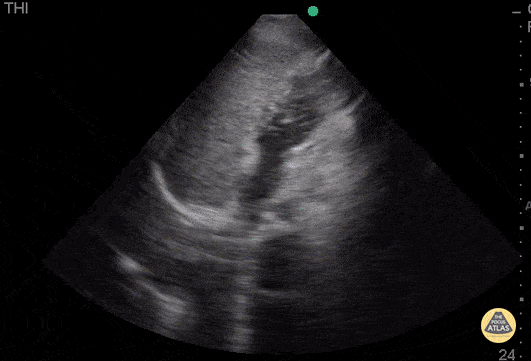

WCUME 2017 submission for "Novel Indication" Bubble test reveals an atrial septal defect seen as bubbles floating from the right side of the heart to the left side. An obvious defect can be seen. Dr. Mojtaba Chahardoli - Firoozgar Hospital